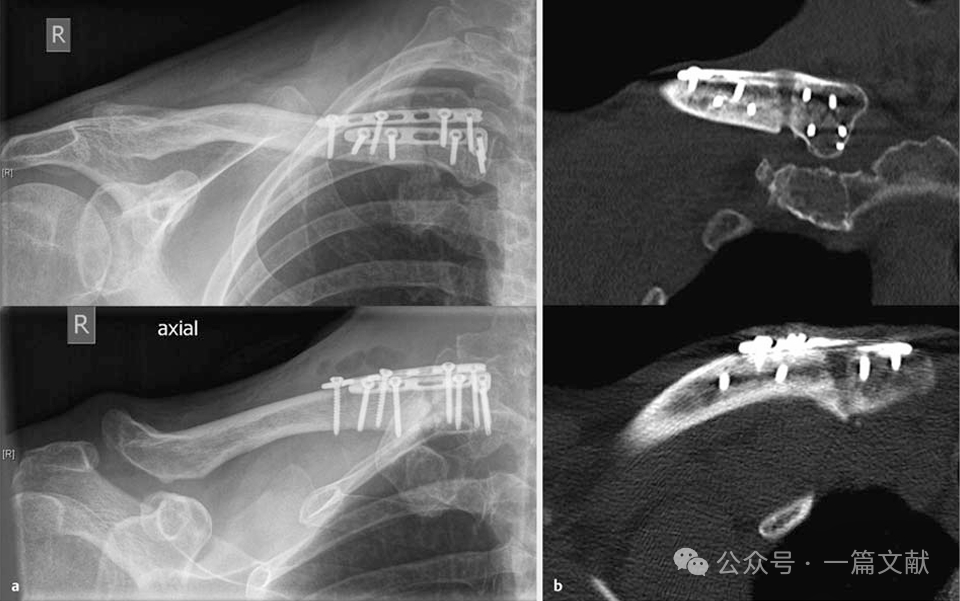

4.1 锁骨骨折的双钢板固定:常用于锁骨骨不连的翻修手术,或锁骨近端骨折的固定。如下图,

锁骨近端骨折术后8周,出现肥大性骨不连,内固定失效。

2.4,2.7mm LCP 双钢板翻修手术,10个月骨性愈合。